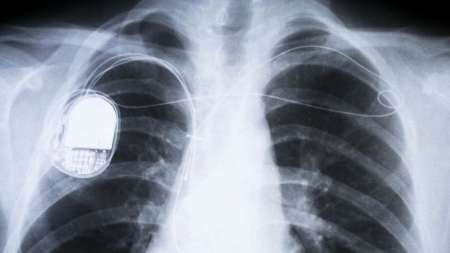

دستگاه ضربانساز، یک دستگاه الکترونیکی کوچک است که معمولا در قفسه سینه یا شکم بیماران قلبی ایمپلنت میشود و از طریق الکترودهایی که به ماهیچههای قلب بیمار متصل میشوند، پالسهای الکتریکی را به این عضلات وارد میکند تا ضربان قلب را تنظیم کند.

نمونههای جدید دستگاه ضربانساز قابلیت برنامهریزی با استفاده از یک نرمافزار واسط را دارند و امکان انتخاب شدت ضربان قلب را برای هر بیمار بهطور اختصاصی فراهم میکنند.